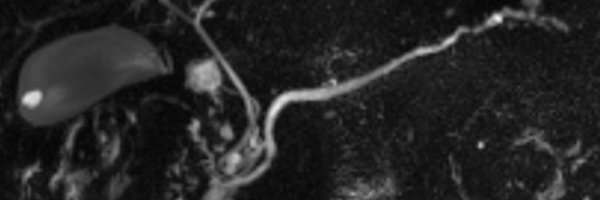

Serous cystic neoplasm (SCN) aka serous microcystic adenoma! Benign, honeycomb-appearing pancreatic cystic mass, usually older female patients, multiple (>6) tiny (<2cm) cystic lesions, may enlarge slowly over time, central scar with calcifications can 'seal the deal' but not